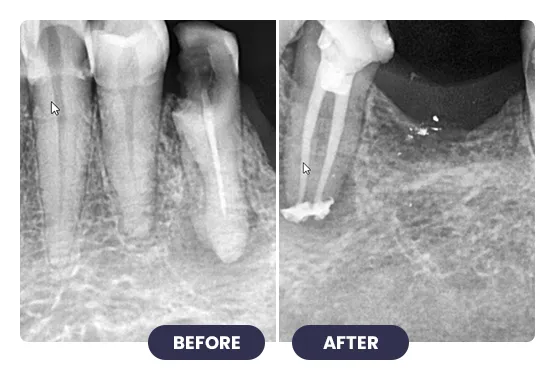

Treating infected or damaged teeth with root canal treatment at iCube Dental is a precise, technique-sensitive procedure that requires professional expertise and careful planning.

Advanced tools and methods are used to remove infection, clean the tooth canals, and restore tooth structure. This treatment relieves pain, prevents further infection, and preserves your natural tooth, ensuring proper bite and chewing function.